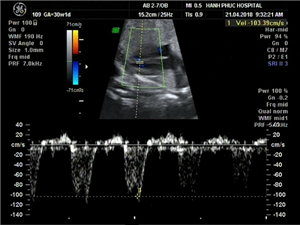

Ca lâm sàng: Thai ở sừng chột của tử cung một sừng